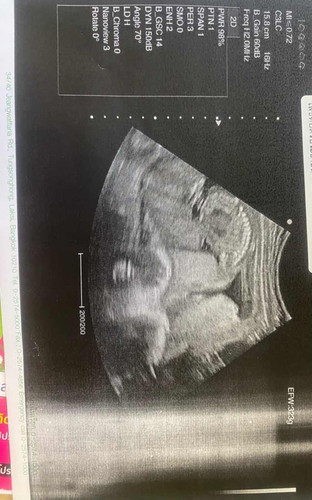

เพศอะไรคะแบบนี้แม่ๆ

ไปซาวด์มาวันนี้ครบ 20 สัปดาห์พอดีคะ แต่หมอไม่บอกเพศ แบบนี้ดูออกไหมคะเพศอะไรแม่ๆ